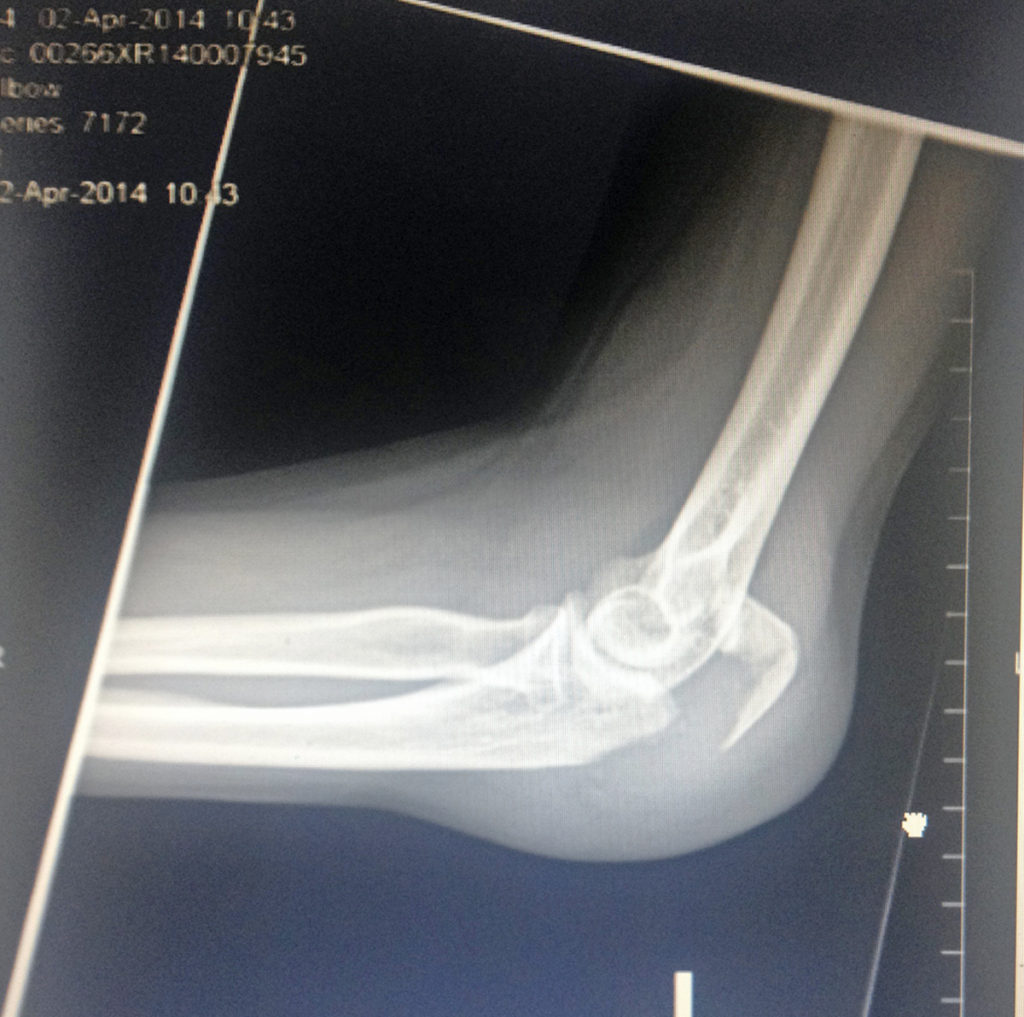

Β I experienced my first ride to the ER in an ambulance.Β I had a concussion, a broken nose,Β a broken elbow, two bulged disks in my Cervical spine and lower back…and I was going to need surgery! …and time to heal.

April 2, 2014 – I woke up early in the morning to go for a short bike ride. I turned on my Strava to record my miles and off I went. I was a bit over 20 miles and already riding back home. About a half a mile after I turned right on Jefferson, I fell off my bike. A few seconds before I fell off, I saw what looked like a black water hose in between the bike lane. It was kind of a diagonal way between the bike lane. I knew I had to do something to try to avoid it but everything happened so fast that I just couldn’t do anything. I do remember thinking to move to the left to avoid touching it but I didn’t have the chance to even look back and check if a car was coming behind me. Moving to the right wasn’t an option. It was too narrow, so by the time I wanted to do something, it was too late. As soon as my front bike tire touched this black thing, (it ended up being a traffic counter. I will tell this other story later) the front tired slid and moved abruptly to the right. I stumbled and next thing I know, I was flying over my bike. I landed with my forehead on the asphalt. My whole body bent down from my neck down.Β That is all I remember. When I woke up, I saw a lady and another person trying to help me. One of them asked me if I knew a phone number so they could call my family. I only remembered my house phone number (we have had this phone number for years) and I passed out again…lol When I opened my eyes again, I saw a lot of people around me. The firefighters and an ambulance were there. Then when my sister said my name, I turned my head to the left. Things do happen like in the movies! I saw my sister’s face but all around it was cloudy. I remember asking her: “como llegaste aqui?”Β (How did you get here?)Β Then the firefighters asked me if I knew what day it was…? I couldn’t remember. They also asked me if I felt my legs. I am glad I did! I guess they noticed I was a bit disoriented so they decided to take me in an ambulance to the ER. Once in the ER, I do remember that my left hip was hurting a lot. I thought I had broken my hip but I had X-Rays, a CT scan and thank God all was ok, except my left elbow. It needed surgery. My elbow was so swollen that they couldn’t do the surgery right away.

I had my surgery on April 17th.